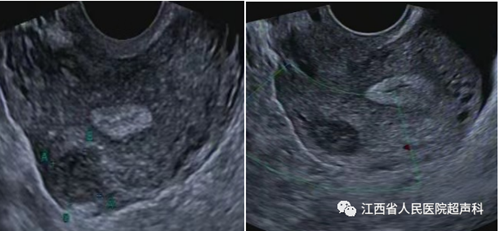

超声检查是公认的首选检查,能准确的观察到子宫的大小、形态,肌瘤的有无。MRI检查能发现直径0.3 cm的肌瘤,对于肌瘤的大小、数量及位置能准确辨别,是超声检查的重要补充手段。经阴道超声检查最常用。但对超出盆腔的肿物、肥胖及无性生活女性适用传统的经腹壁超声检查。

超声引导下微波消融术是利用微波的局部致热效应,在短时间内使针型辐射器周围的组织温度升高至可以使组织细胞蛋白质发生凝固性坏死的高温,造成组织细胞不可逆性凝固坏死,实现在保留子宫基础上达到子宫肌瘤组织和细胞原位灭活、肌瘤缩小或经自然腔道排出体外完全消失的治疗目的。